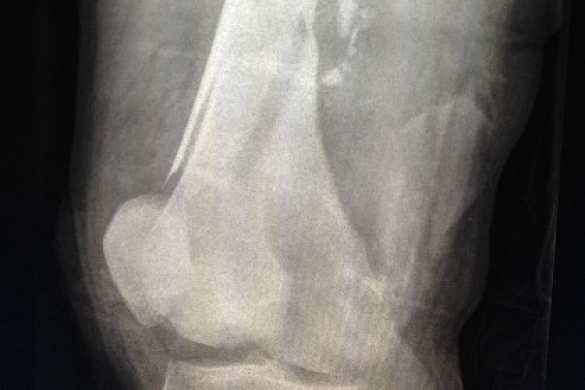

В своей работе инженеры для имитации кровоизлияния в поврежденной части человеческого тела использовали гидродинамику сглаженных частиц. Для этого с учетом необходимых анатомических особенностей (расположения костей, мышц, сосудов и кожи) исследователи провели трехмерную реконструкцию человеческой ноги.

На примере деформированной баллистическим снарядом человеческой ноги специалисты изучили процессы внутреннего и внешнего кровоизлияний. Инженеры рассмотрели два сценария ранения: в первом случае нога человека расположена вертикально, тогда как во втором случае она расположена горизонтально.